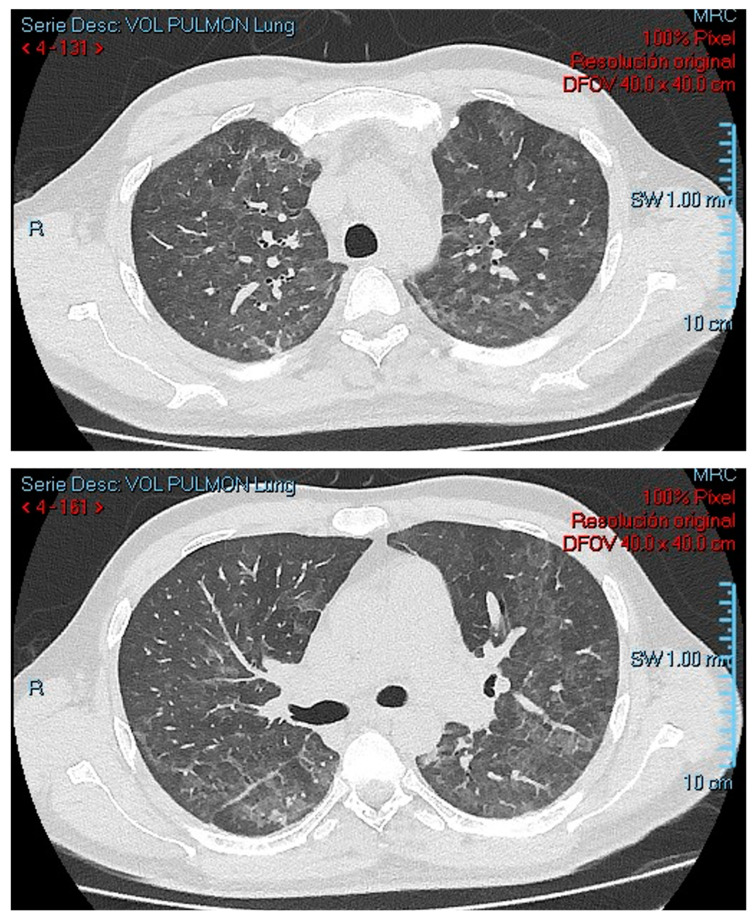

Methods: We describe the case of a 34-year-old man newly diagnosed with HIV/AIDS, presenting with severe immunosuppression and Pneumocystis jirovecii pneumonia. The patient initially improved with cotrimoxazole and corticosteroids, but was readmitted shortly after discharge with abdominal pain, diarrhea, and worsening pancytopenia. A bone marrow biopsy revealed Pneumocystis jirovecii cysts, confirming disseminated infection. Concomitant Kaposi sarcoma involving the skin and gastrointestinal tract was also diagnosed. Despite antimicrobial therapy, the patient's condition worsened, leading to multisystem organ failure and death two months later.

Conclusions: This case highlights a rare presentation of disseminated Pneumocystis jirovecii infection with bone marrow involvement in a patient with advanced HIV/AIDS. Although infrequent, this complication should be considered in individuals with Pneumocystis jirovecii pneumonia who develop persistent cytopenias and systemic symptoms. Diagnosis depends on histopathologic confirmation, which may lead to under-recognition. Early suspicion and individualized management are essential, though the optimal treatment approach for extrapulmonary infection remains undefined.